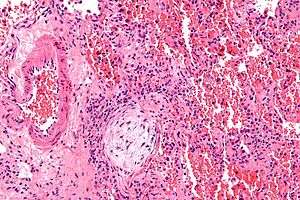

Micrograph showing a Masson body (off center left/bottom of the image – pale circular and paucicellular), as may be seen in bronchiolitis obliterans organizing pneumonia. The Masson body plugs the airway. The artery associated with the obliterated airway is also seen (far left of the image). H&E stain. | |

Histologically, cryptogenic organizing pneumonia is characterized by the presence of polypoid plugs of loose organizing connective tissue (Masson bodies) within alveolar ducts, alveoli, and bronchioles.